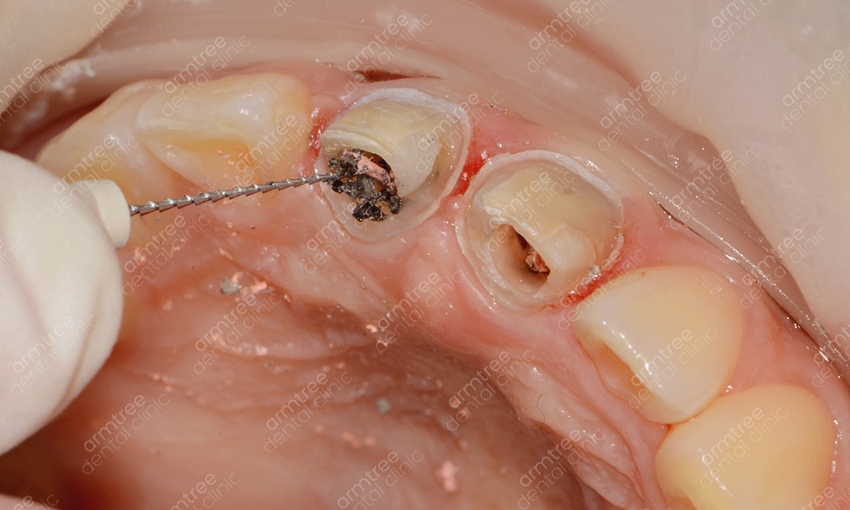

신논현역 치과 아름드리치과에서 실활치미백을 진행하는 과정을 알려드릴께요. 먼저 치아 내부의 신경과 혈관 등이 괴사한 경우라면 신경치료를 우선적으로 진행해요. 신경치료를 마무리 한 후 입술보호제를 꼼꼼히 발라주고 신경 쪽을 막은 뒤 미백제를 투여하는 과정을 진행해요. 충전된 미백제 입구를 막고 상태를 지켜본 뒤 간격을 두고 미백약제를 교체하여 몇 번의 과정을 반복해주어요. 물론 개인차가 존재하지만 대략 2-3회 정도 반복 과정을 한 뒤 미백이 완료되면 입구를 레진으로 수복하여 마무리를 해요. 치아미백을 하시고 난 후 외관상으로 다른 부작용은 없으나 간혹 약간의 시림증상이 발생할 수 있는데요. 하지만 일정 시간이 지나면 곧 괜찮아 지며 변색의 정도가 심해 미백으로 개선이 어려울 시 라미네이트도 대안이 될 수 있다는 걸 알아두세요. 앞니변색으로 인하여 미백을 진행할 경우 하얀 치아로 개선하는 것도 중요하겠지만 다른 치아와의 컬러 밸런스가 필요해요. 하나만 홀로 하얗다면 검거나 누런 것과 비슷하게 심미적으론 좋지 않기 때문에 색상 조절을 잘 해줄 수 있는 전문적인 의료기관을 선택해야 하겠어요.